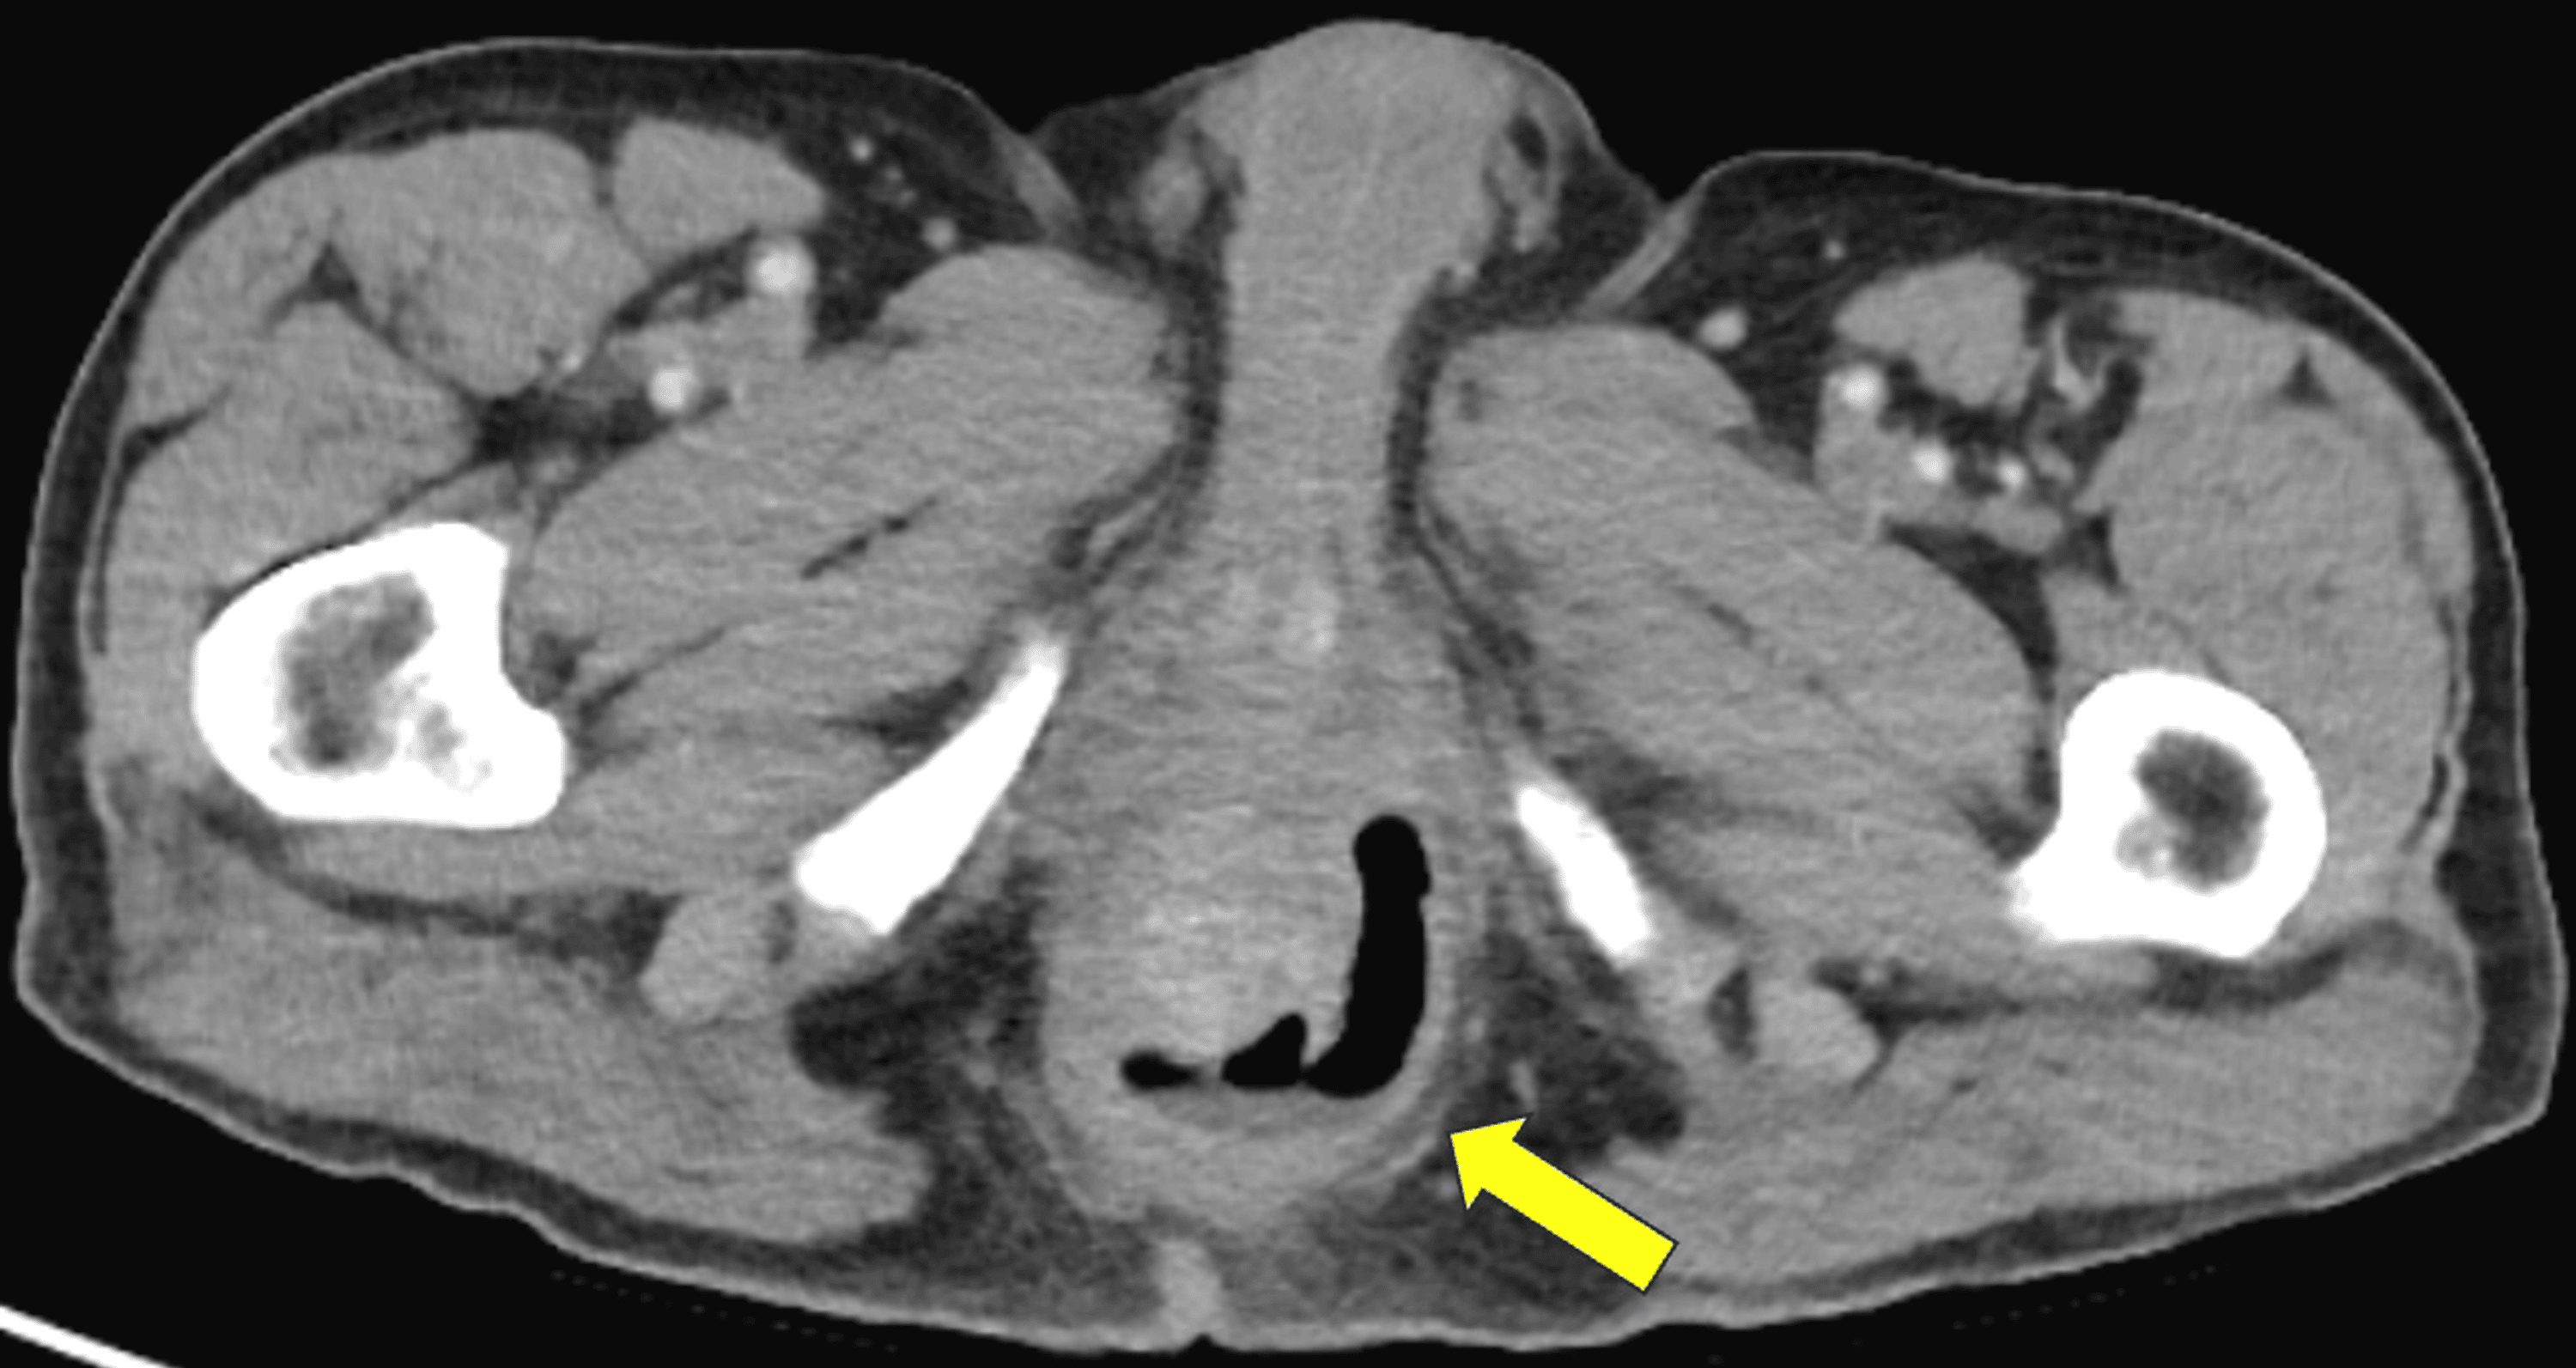

Cureus Horseshoe Abscess as a Rare Complication After Transanal Hemorrhoid Dearterialization Web transanal hemorrhoidal dearterialization (thd) is an effective treatment for hemorrhoidal disease (hd). Web our aim is to analyze the outcomes following transanal hemorrhoidal dearterialization (thd) procedure. Web transanal hemorrhoidal dearterialization (thd) is a minimally invasive procedure to remove hemorrhoids. Web the transanal hemorrhoidal dearterialization (thd) doppler procedure is a minimally invasive technique to treat. Web thd is based on. Hemorrhoid Dearterialization.